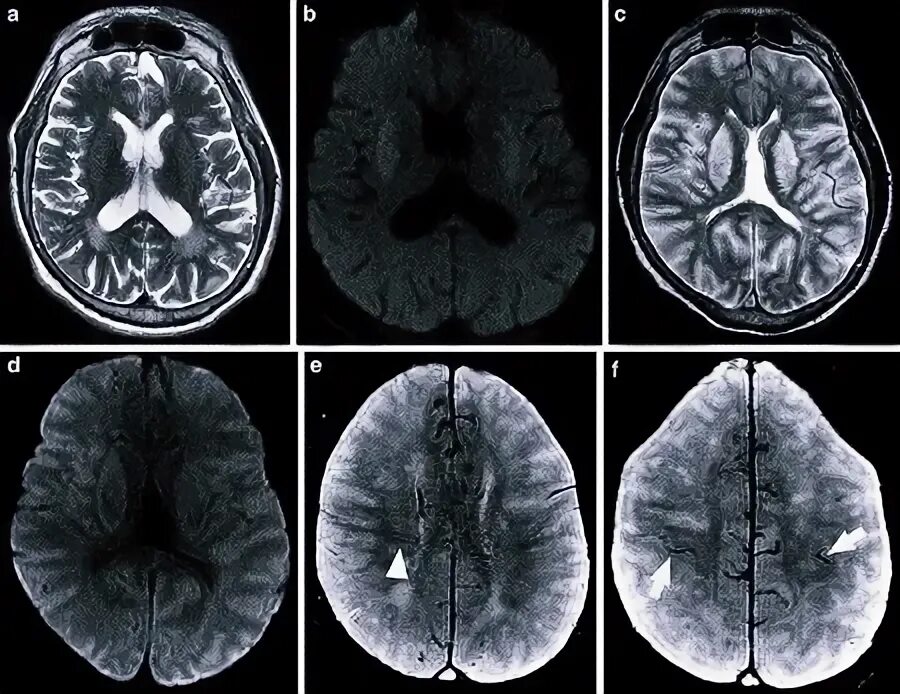

Диффузно атрофические изменения головного